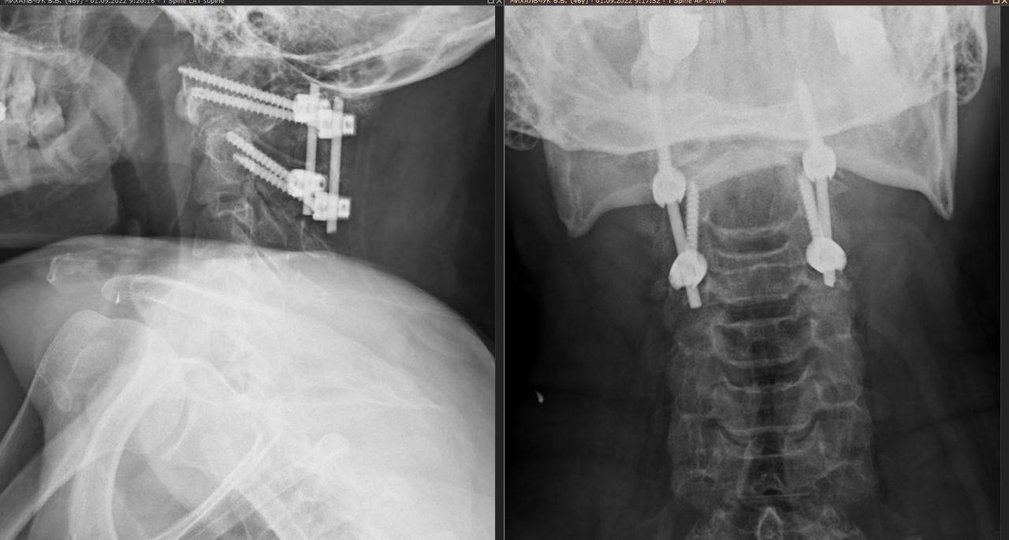

Суть операції полягає у тому, що перший і другий шийні хребці вправляються та фіксуються між собою гвинтово-стрижневою конструкцією. Це оперативне втручання на шийному відділі хребта вважається одним із найскладніших через близьке розташування життєво важливих структур таких, як хребетна артерія, пошкодження якої може призвести до інсульту у вертебро-базилярному басейні, та шийний відділ спинного мозку, травма якого може стати причиною глибокої інвалідизації чи смерті пацієнта, – йдеться у повідомленні.